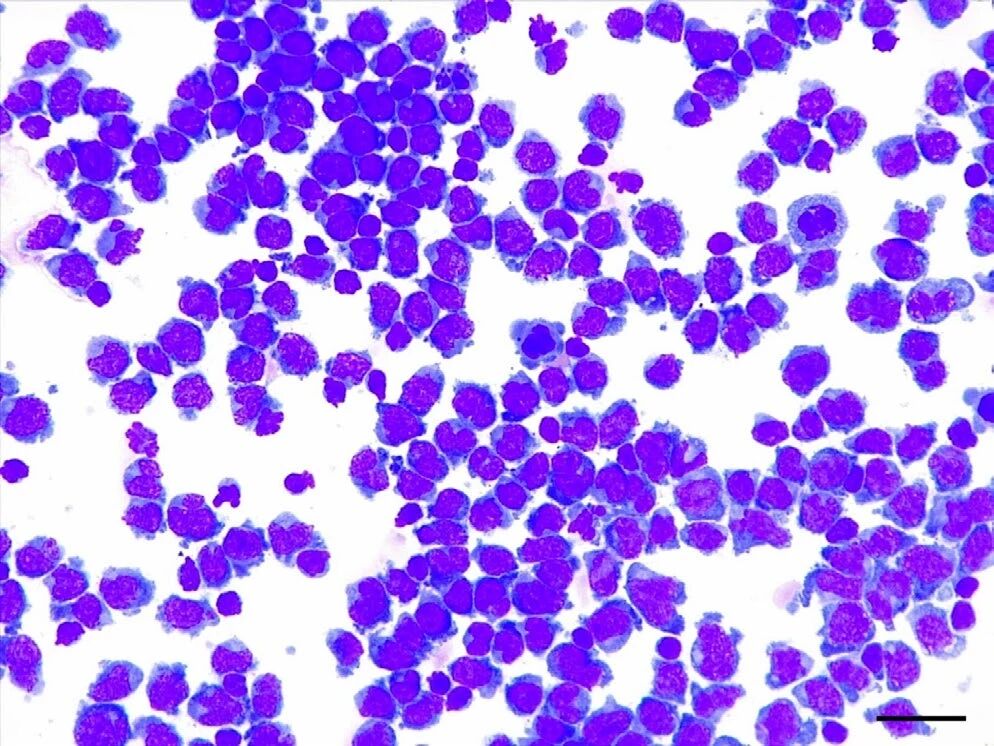

通过腰穿获得的脑脊液分析显示,淋巴细胞明显增多(837个/μL,蛋白14843.8mg/L),以中等和大型淋巴细胞为主,小型成熟淋巴细胞数量少(<20%),有罕见的有丝分裂象(下图)。这些发现提示为中等到大细胞淋巴瘤。

↑ 脑脊液的细胞学分析显示高度细胞增生,以中型和大型淋巴细胞为主,且小型成熟淋巴细胞数量较少。